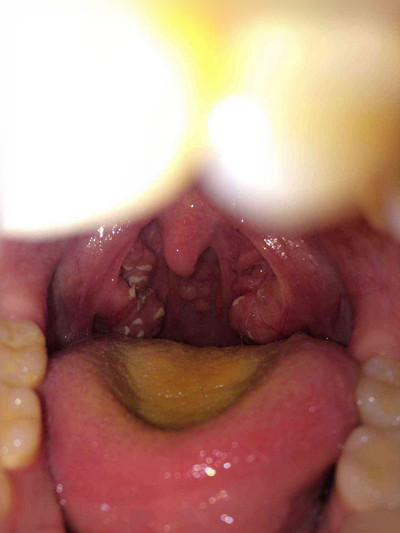

扁桃體週膿腫相關文章

扁桃體週膿腫相關問答

A:患者出現扁桃體周圍膿腫,需要進一步做膿腫的穿刺抽膿治療。穿刺抽膿操作前,要使用利多卡因等局麻藥物在穿刺點附近黏膜表面進行局部麻醉,麻藥充分起效後,使用穿刺的粗針頭接注射器,從膿腫的最隆起處刺入,然後抽吸出膿液。要注意穿刺的角度不要太向外側,……

A:扁桃體周圍膿腫也是耳鼻喉科很常見的一個疾病,因為扁桃體感染髮炎形成了周圍膿腫。患者出現咽部異物感、疼痛、口腔有血性分泌物,可以在門診進行切開引流術,切開引流後配合抗生素使用是可以恢復的。這個費用大概需要500塊錢左右,但是要根據當地的消費水……

A:扁桃體周膿腫一旦形成,要膿腫切開引流,加抗炎治療。首先要用注射器穿刺膿腔,抽出膿液,確診膿腫形成。在穿刺點周圍黏膜局麻,用手術刀切開粘膜肌肉,進入膿腔,會有膿液湧出,用大的止血鉗,插入膿腔,擴大膿腔切口,使更多的膿液流出來,同時用注射器,鹽……